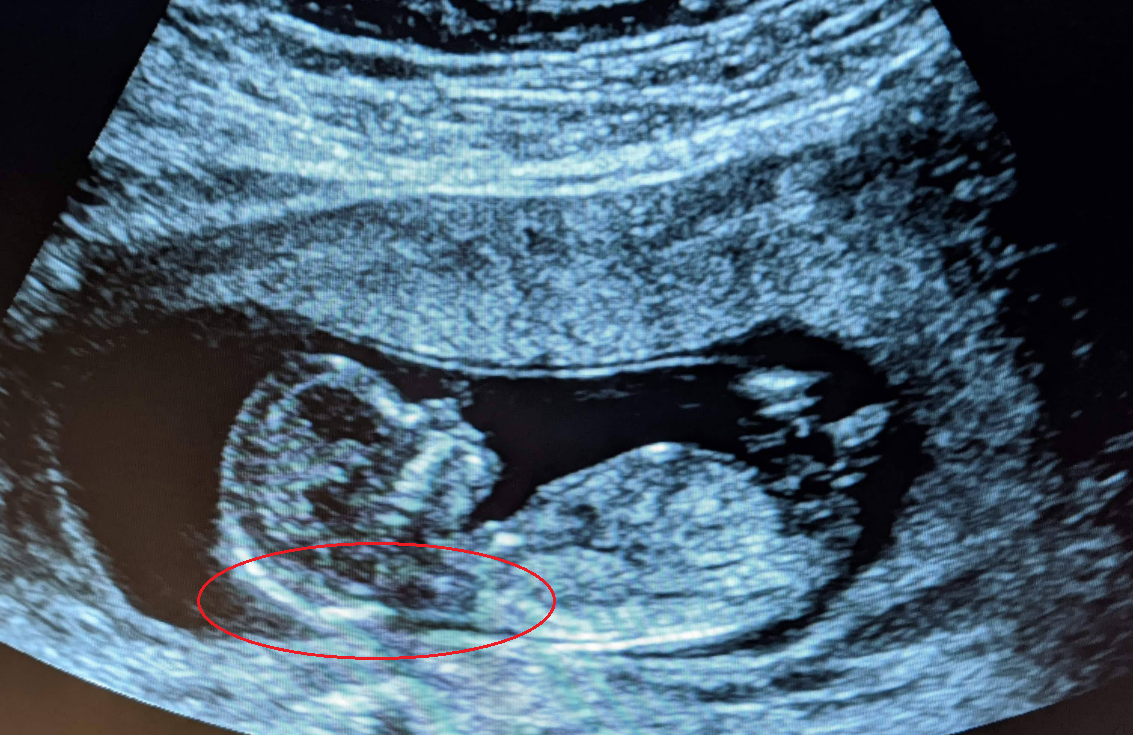

Abnormal nuchal translucency normal baby. The NT grows in proportion to the baby. A special ultrasound called a nuchal translucency ultrasound is performed between the 11th and 14th weeks of pregnancy. So a normal NIPT result does not guarantee a healthy baby and an abnormal result does not mean your baby definitely has a certain condition.

An NT scan is a common screening test that occurs during the first trimester of pregnancy. For a baby that is between 45 mm and 84 mm in size a normal measurement is anything less than 35 mm. Less than 6 mm is considered normal up to 22 weeks.

A nuchal translucency screening or NT screening is a specialized routine ultrasound performed at the end of the first trimester of pregnancy. Doctors were very apologetic about the error but we were still considering complaining as initially we felt an invasive procedure that increased risk of miscarriage was done for no reason. Nuchal Translucency was 16mm so within normal ranges.